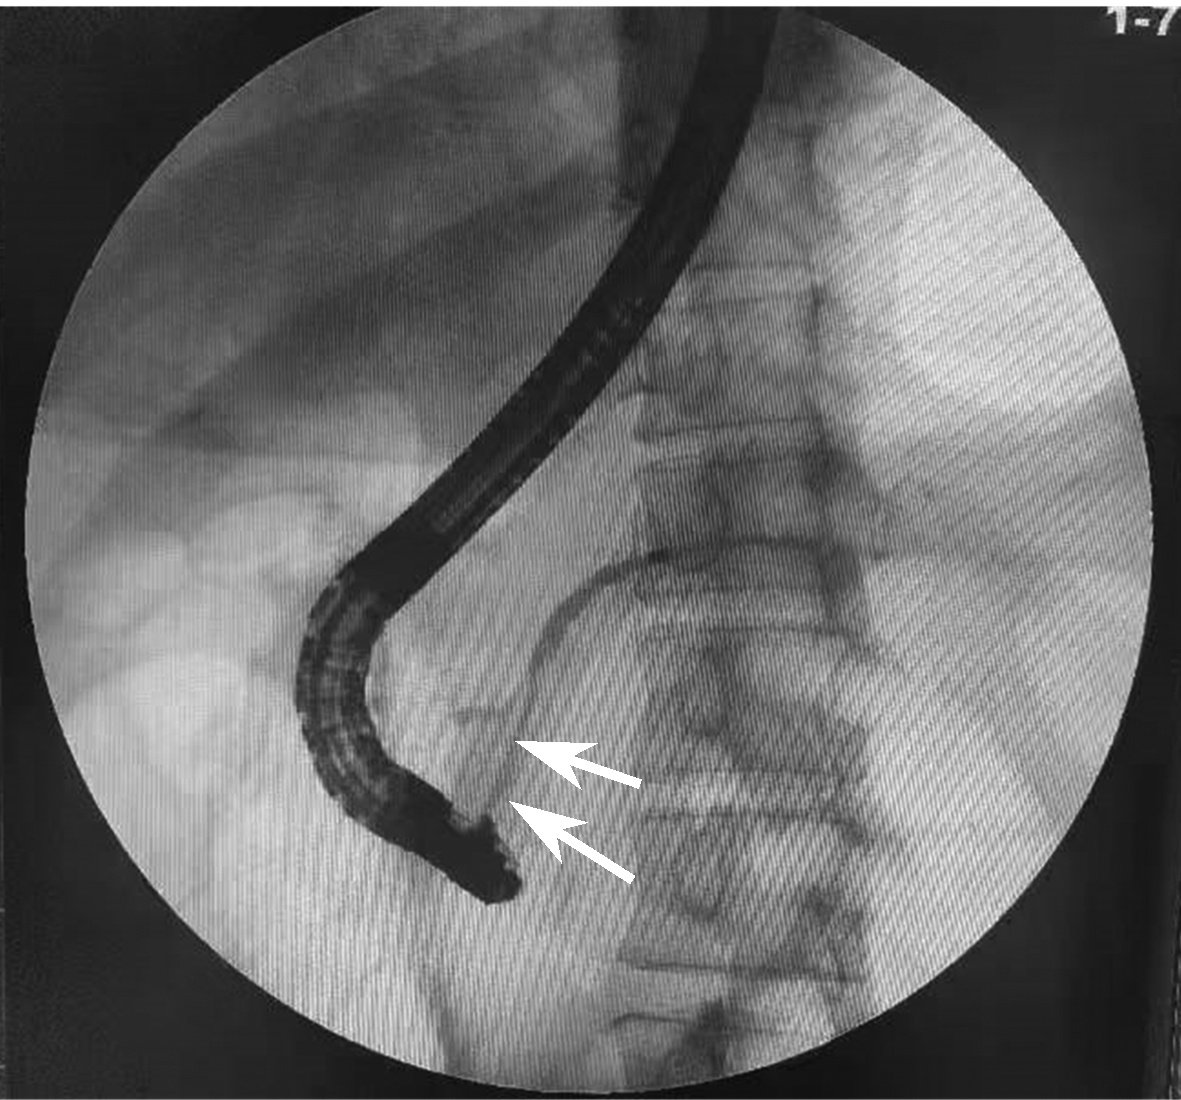

胰管结石治疗方案的选择分析与比较

2022, 38(11): 2558-2564. DOI: 10.3969/j.issn.1001-5256.2022.11.023

摘要(887) HTML (968) PDF (2050KB)(104)

摘要:

目的  收集并对比分析内镜逆行胰胆管造影(ERCP)、腹腔镜术和开腹手术三种方案治疗胰管结石(PDS)患者的临床资料及治疗效果,总结PDS治疗方案选择的经验,进一步研究探讨可行的使患者获益最大化、最优化的治疗方案。  方法  回顾性分析2014年6月—2018年12月海军军医大学附属公利医院治疗的131例PDS患者的临床资料。根据手术情况分为3组:ERCP组69例,腔镜组32例,开腹组30例。监测3组患者手术前后相关指标的变化;进一步对比分析腔镜组和开腹组的手术疗效。正态分布的计量资料两组间比较采用独立样本t检验;多组间比较采用单因素方差分析,进一步两两比较采用LSD-t检验或SNK-q检验。偏态分布的计量资料两组间比较采用Mann-Whitney U检验,多组间比较采用Kruskal-Wallis H检验。手术前后相关指标差异比较采用重复测量资料的方差分析和Friedman检验。计数资料组间比较采用χ2检验。  结果  131例PDS患者中Ⅰ型40例、Ⅱ型76例、Ⅲ型15例。腔镜组与开腹组主要手术方式的病例数比较差异无统计学意义(χ2=1.93,P>0.05)。腔镜组和开腹组血WBC、CRP、PCT、HOMA-IR在手术前后的动态变化存在明显差异(F=24.68、χ2=227.66、F=45.37、F=106.71,P值均<0.05)。腔镜组手术时长、术中出血量、术后首次排气时间、术后止痛药物应用频次、腹腔引流管拔除时间、术后近期并发症、术后平均住院时长等观察指标均较开腹组明显减少/缩短(t=-4.80、t=-9.43、Z=-6.78、t=-11.59、Z=-6.77、χ2=9.24、t=-3.60,P值均<0.05)。ERCP组、腔镜组、开腹组术后近期并发症发生率分别为24.64%、28.13%、66.67%,差异有统计学意义(χ2=17.12,P<0.05);ERCP组及腔镜组术后近期并发症发生率均显著低于开腹组(χ2值分别为15.78、9.24,P值分别为<0.05、0.02)。ERCP组、腔镜组、开腹组治疗有效率分别为91.30%、93.75%、73.33%,3组间有效率差异有统计学意义(χ2=7.70,P=0.02),ERCP组及腔镜组有效率均好于开腹组(χ2值分别为5.56、4.77,P值分别为0.02、0.03)。  结论  ERCP为临床微创治疗部分Ⅰ、Ⅱ型PDS的首选治疗方法,安全有效、严重并发症少。外科手术是治疗复杂型PDS的重要手段,但技术复杂、操作难度大。腹腔镜术较开腹术创伤小、严重并发症少,腹痛缓解率高,可以显著减少手术时长、降低术中出血量及缩短术后平均住院时长。针对复杂型PDS宜优先选择腹腔镜术治疗。